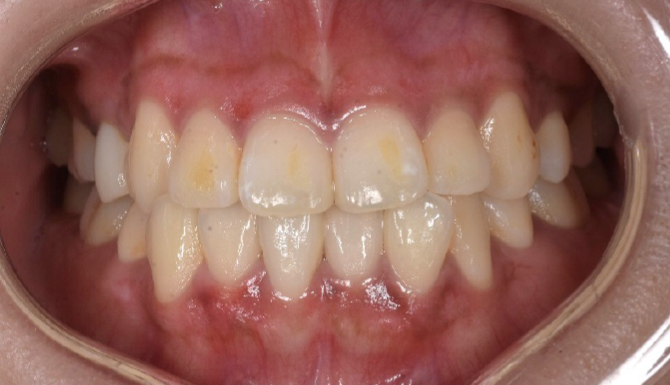

CASE2

Before

After

年齢・

性別

20代・男性

主訴 歯ぐきの色が気になる

治療

回数

1回

費用

ガムピーリング 上下顎

11,000円×1

(2025年9月現在)

内容

ガムピーリング

リスク・

副作用

・ヒリヒリとした痛み

・フェノール、アルコール類にアレルギーは禁忌

・施術後1〜3日くらいは歯ぐきが白っぽくなる